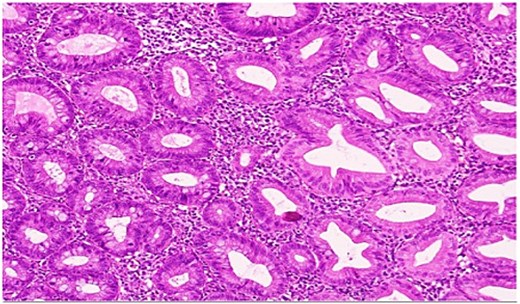

She underwent an uncomplicated laparoscopic appendectomy. Histopathology confirmed acute appendicitis and incidentally identified a serrated polyp confined to the mucosa without dysplasia or malignancy (Figs. 2—4). Postoperative recovery was uneventful; she was discharged stable and asymptomatic at 2-week follow-up. Given the incidental finding, colonoscopic evaluation was arranged to assess for synchronous colorectal lesions.

Low-power hematoxylin and eosin-stained sections of the appendix (4× and 10× magnification) demonstrating prominent crypt serration within the appendiceal mucosa with the characteristic saw-toothed crypt architecture and increased mucin production.

High-power view showing comparison of the adjacent normal appendiceal mucosa with unremarkable straight crypts lining the lumen and the serrated architecture of the polyp.

High-power magnification highlighting the serrated configuration of the crypt epithelium in detail, with luminal tufting and goblet cell-rich lining.